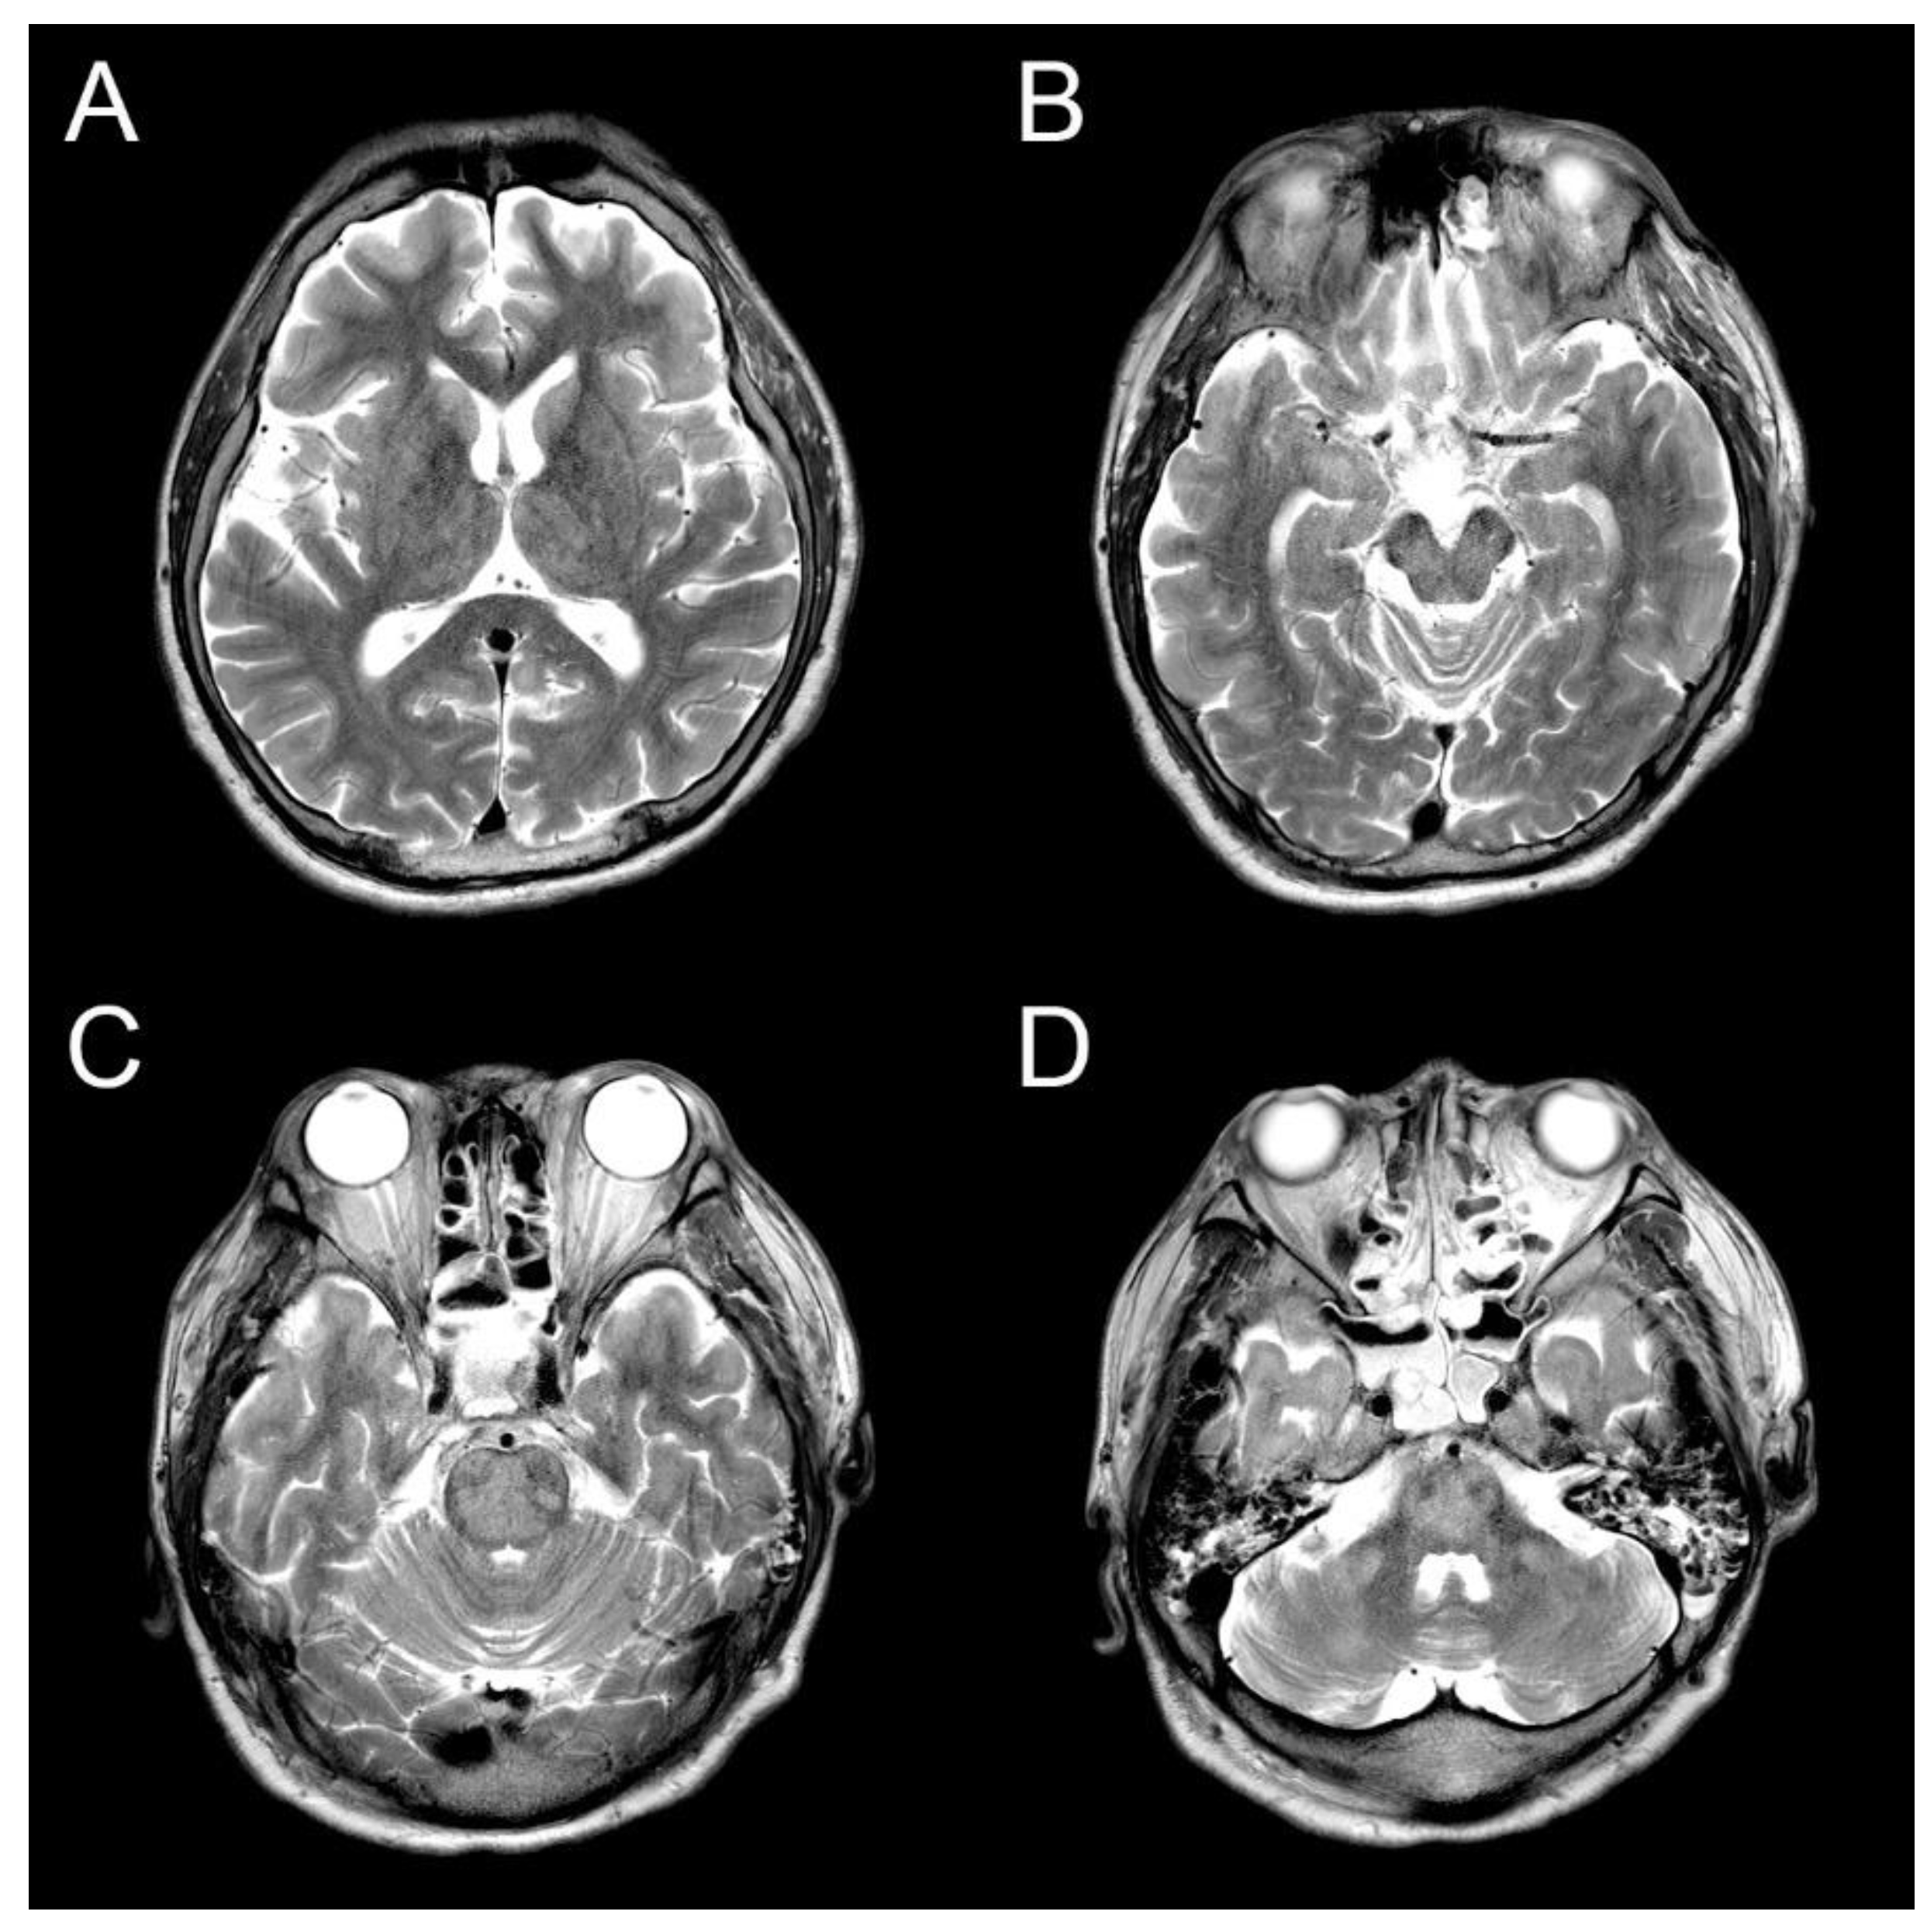

The ammonia level was initially controlled with lactulose enema, and the level was normal range on the third day of hospitalization. However, there was still no change in consciousness state. Also, progressive spastic quadriparesis and ophthalmoplegia was observed. Electroencephalography (EEG) results were continuous slow and generalized, and follow up brain MRI on the 14th day showed high signal intensity at bilateral caudate nucleus, putamen, thalami, midbrain, central pons and bilateral middle cerebellar peduncle on T2-weighted MRI (Figure 1). The lesion with no mass effect showed hypointense on T1-weighted MRI. Contrast enhancement is not seen in lesions. These were all new findings compared to prior brain MRI during the same admission. During these periods, electrolyte levels including sodium level maintained in normal range. It was diagnosed that the ODS was secondary to rapid correction of hyperammonemia and hyperbilirubinemia without changes in serum sodium level. Consciousness was still stupor and hyperbilirubinemia was shown during conservative manegement. The guardians did not agree to additional hemodyalysis and the transplantation of the liver. Eventually, he died on the 76th day of hospitalization due to severe metabolic acidosis.

Figure 1. Osmotic demyelination syndrome at (A) bilateral caudate nucleus, putamen, thalami, (B) midbrain, (C) central pons and (D) bilateral middle cerebellar peduncle on T2-weighted magnetic resonance imaging in brain on the 14th day after rapid correction of hyperammonemia and hyperbilirubinemia.